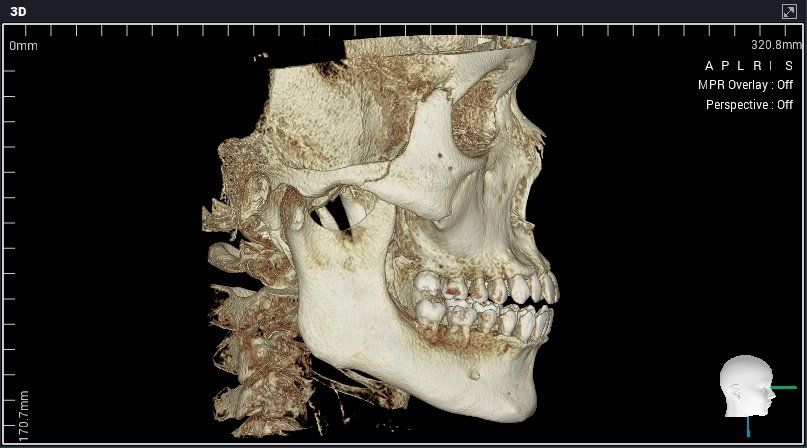

미세돌출입 때문에 3군데에서 교정상담을 받았는데 치아교합이 전체적으로 좋고 치아각도도 좋다고 했습니다 대신 앞니치근이 짧고 약간의 하악비대칭이있다고 했습니다.

A치과는 평균남성보다 하관이 크고 조금 턱이 나와서 입이 전체적으로 나와보이는 거라서 구강악안면외과가서 양악이나 윤곽수술상담을 받아보라고 했습니다.

세가지 치과 모두 맞는 말입니다. 지금 보여주신 자료를 종합해보면 경미한 3급 부정교합입니다.

이 상태에서 교정도 가능하고 양악도 가능하지만 치료 이후 변화되는 모습에는 한계가 있습니다. 또한 부정교합 및 골격부조화가 심하지 않으므로 심미적으로 불편감이 없다면 3번 치과처럼 치료하지 않아도 됩니다. 물론 심미적으로 문제가 된다고 생각한다면 이때는 두가지 방법 모두 가능합니다.

다만 양악수술은 확실히 골격 부조화를 잡아줄 수 있다면 교정에는 한계가 있으니 전문가와 상담이 필요합니다.